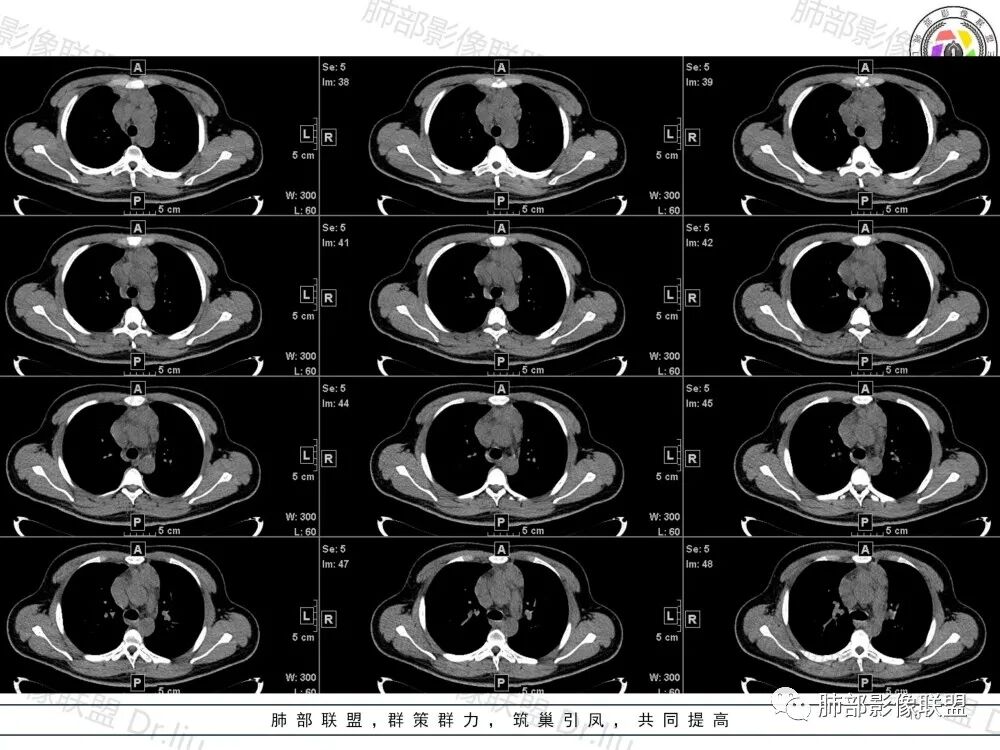

2、影像特点:两肺可见多发大小不一的结节影,部分结节周围可见晕征,部分结节沿着支气管血管束分布,部分位于胸膜下。前纵隔内可见多发结节样软组织密度影,边界不清,部分病灶融合倾向,其脂肪间隙显示模糊。由于腹腔层面少,未能确定腹腔内有无增大淋巴结,需要连续层面追踪观察。

3、病例小结:年轻男性+前纵隔多发结节样软组织影+双肺多发结节,需要警惕淋巴瘤,至于多数老师提到鉴别结节病,结节病以双肺门对称性淋巴结肿大为典型表现,其肺内表现多为沿肺门旁支气管血管周围间质分布的多发结节,结节病可表现纵隔内多发淋巴结肿大、且淋巴结密实,孤立少融合,该病例中均缺乏以上特点,另外结节病好发中青年女性,此病例年龄亦不符合。